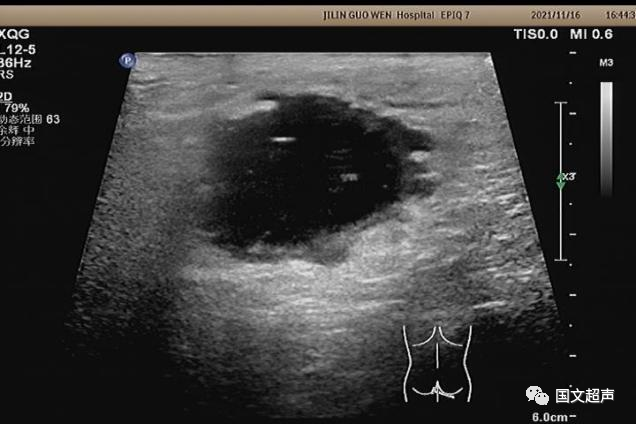

肛周:7點(diǎn)鐘方向皮下脂肪層內(nèi)探及不均質(zhì)低無回聲包塊,范圍約4.6*3.0cm,較淺處距體表約0.6cm,邊界不清,周圍軟組織回聲增強(qiáng),CDFI:周邊血流信號(hào)豐富,輕加壓探頭有涌動(dòng)感,如下圖: